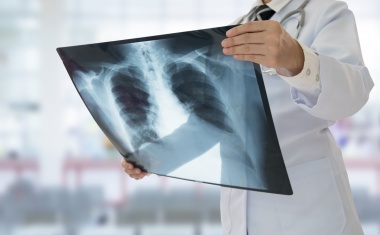

An den Oberhavel Kliniken müssen Patienten keinen Röntgenschutz mehr tragen

Moment, fehlt da nicht noch etwas? Die Medizinische Technologin verlässt den Raum, um die Röntgenaufnahme vom Brustkorb zu starten, aber dieses schwere Teil von den vorigen Malen ist noch gar nicht um die Hüfte gelegt worden.